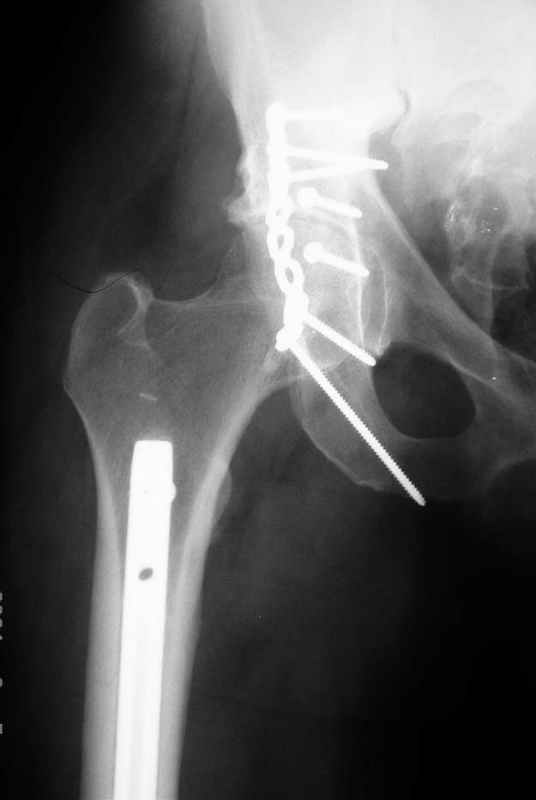

>Все-таки решил остановиться на одноэтапном подходе и спустя 5 дней

>(как раз и наборы привезли) из расширенного илеофеморального доступа

>сначала фиксировал реконструктивным штифтом Smith&Nephews бедро и

>шейку (благо перелом шейки 2 типа -относительно стабильный) затем

>фрагмент крыла подвздошной кости

>Lag screw, далее пластина на заднюю колонну и винты в переднюю колонну.

Пластина на обе колонны и Lag screw с передней к задней, тактика правильная.